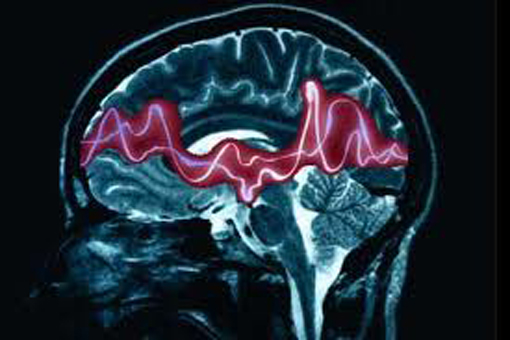

Secondo i dati emersi da un recente studio pubblicato sulla rivista Jama Neurology a cura di numerosi esperti internazionali, tra cui il prof. Harald Aurlien, tra i relatori al Congresso, mostrano come la valutazione dell’EEG con l’Intelligenza artificiale sia in linea con la refertazione effettuata da esperti, ma i cui risultati vanno ancora rivalutati da un occhio umano esperto. Gli Autori, quindi, concludono che in futuro ci saranno buone possibilità di refertare in modo affidabile utilizzando l’IA, e questo è particolarmente utile nei Paesi a basso reddito dove non ci sono elettroencefalografisti esperti o in quelle strutture dove si effettuano molti esami ma non è disponibile personale esperto a sufficienza.

“Gli algoritmi di intelligenza artificiale – spiega Stefano Meletti, Direttore della Struttura complessa di Neurologia e Professore Associato di Neurologia presso l’Università di Modena e Reggio Emilia – possono analizzare i dati dell’elettroencefalogramma (EEG) continuo per rilevare la presenza di una eventuale attività epilettica e prevedere o segnalare l’insorgenza di crisi. Questi modelli predittivi integrano diverse variabili cliniche, come i dati demografici del paziente, le comorbidità, le caratteristiche EEG e le risposte al trattamento, per stimare il rischio di esiti avversi come sequele neurologiche o la mortalità. L’identificazione precoce dei pazienti ad alto rischio può guidare un monitoraggio intensivo e interventi mirati per migliorare gli esiti e ridurre al minimo le complicanze a lungo termine”.